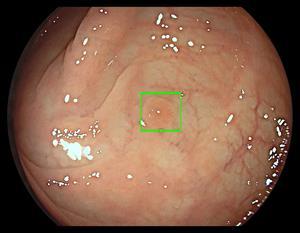

[의학신문·일간보사=김자연 기자] 메드트로닉이 세계 최초의 대장 폴립 감지 인공지능 내시경 모듈인 GI 지니어스를 출시한다고 밝혔다. 이는 대장 내시경 동안 AI를 이용해 실시간으로 전암성 병변의 존재를 자동으로 강조해 줘 제 2 관찰자와 같은 역할을 제공한다. 이를 통해 작고 납작한 폴립 등 감지가 어려운 병변이라도 찾을 수 있어 진단 및 결과를 개선시킬 수 있을 것으로 기대된다. 이번 출시를 위해 메드트로닉은 AI 소프트웨어 및 기기를 개발한 코스모 파마슈티컬스와 세계 유통 계약을 체결했으며 일부 유럽 국가에서 이용이 가능하다.